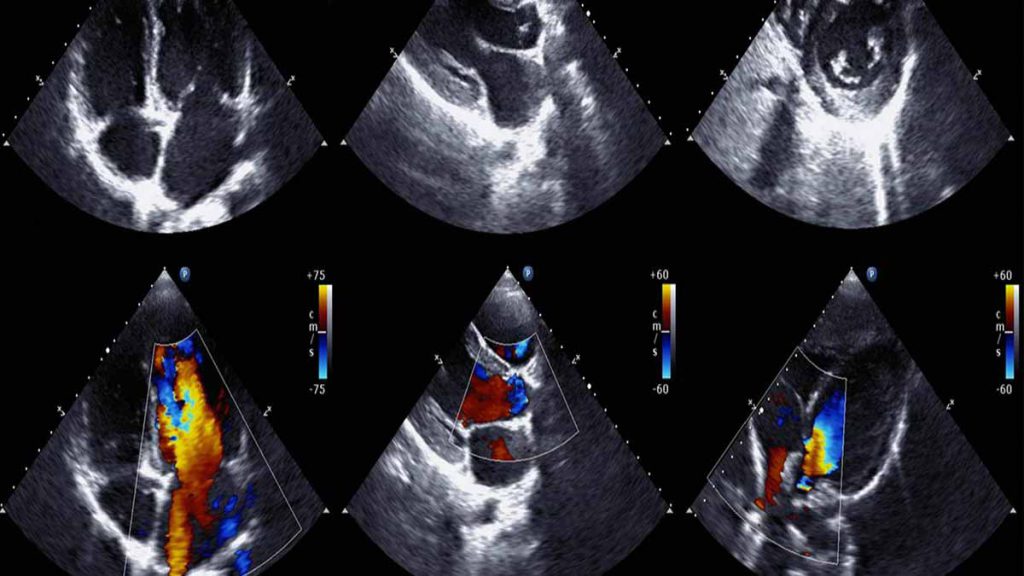

در اکوی قلب یا اکوکاردیوگرام از امواج صوتی برای ایجاد تصاویری از قلب استفاده میشود. این آزمایش رایج میتواند جریان خون از طریق قلب و دریچههای قلب را نشان دهد. پزشک شما میتواند از تصاویر بهدستآمده از این آزمایش برای شناسایی بیماریهای قلبی و مشکلات دیگر قلبی استفاده کند.

اکوی قلب یا اکوکاردیوگرافی (Echocardiography) یک آزمایش تصویربرداری است که به کمک امواج صوتی برای ارزیابی عملکرد قلب و بررسی ساختار آن به کار میرود. در این آزمایش، امواج صوتی با فرکانس بالا به قلب ارسال میشوند و بازتاب آنها به دستگاه اکو برگشت داده میشود تا تصویری از ساختار قلب ایجاد کند. این تصویربرداری میتواند اطلاعات مفیدی در مورد اندازه قلب، وضعیت دریچهها، ضخامت دیوارههای قلب، جریان خون و هر نوع اختلالی که ممکن است در قلب وجود داشته باشد، به پزشک ارائه دهد.

- اکو کاردیوگرافی داپلر: این نوع اکو برای بررسی جریان خون در قلب و عروق خونی استفاده میشود و میتواند مشکلاتی مانند نارسایی دریچهها یا انسداد عروق را شناسایی کند.